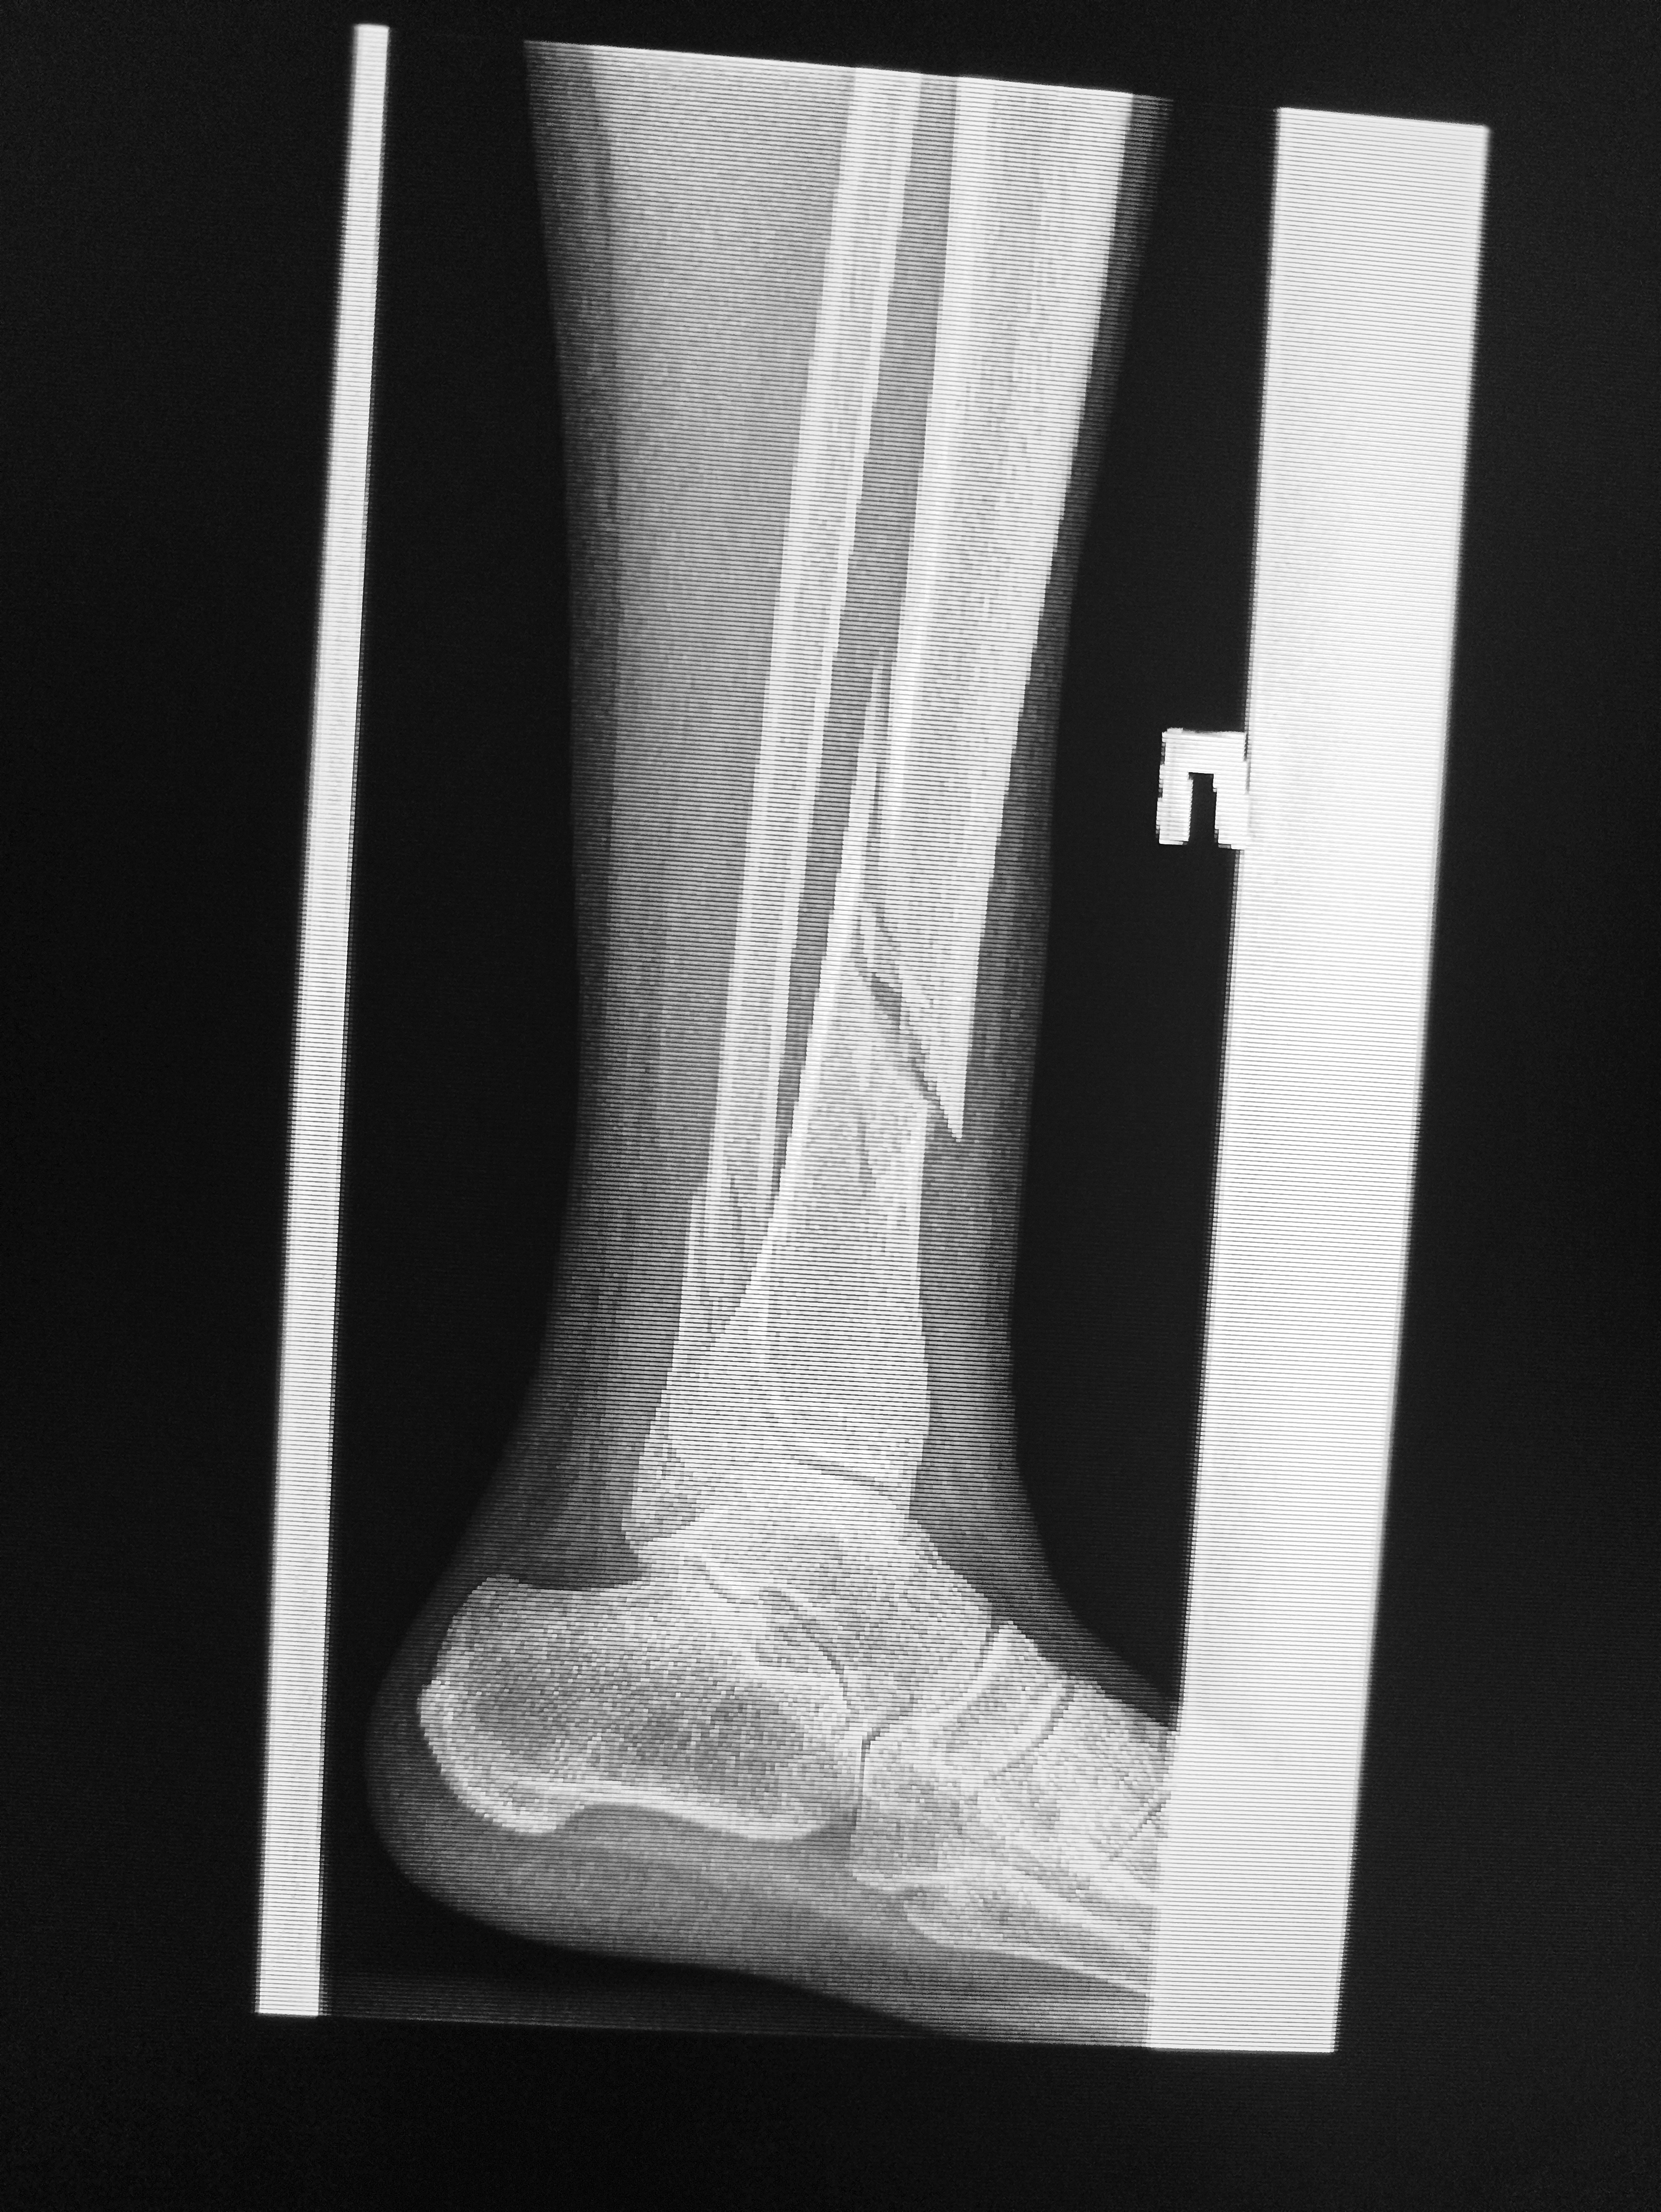

Никогда такой хуйни не было! И вот опять! Здравствуй двачик! Я итт буду с вами играть в рентгенолога, флексить зарплатой 31 к за октябрь и общатся! Давайте дружить! Угадывайте пиздецомы по фоточке и общайтесь ибо я тут чо-то заебалс. Штош погнали!